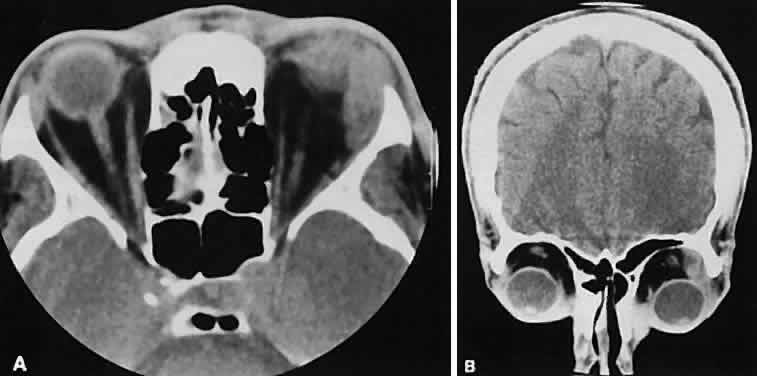

The edema and inflammatory infiltrate that accompany infections are indistinguishable from that associated with orbital inflammations. The presence of sinus disease, however, is a more constant feature with infections, because the sinus represents the infectious nidus in most cases (Fig. 9). In addition to the frequent appearance of sinus disease, the adjacent EOM is invariably enlarged. Less often, orbital infections may be transmitted through the blood, related to a retained foreign body, or spread from the lids. Chandler and colleagues47 classified orbital infections into five groups. Group 1 (preseptal cellulitis) represents inflammatory edema and reflects congestion of venous outflow. Group 2 has actual orbital infiltration/edema with mass effects and functional deficits. Group 3 includes patients with subperiosteal abscesses. Most of these dome-shaped subperiosteal abscesses are located along the medial wall. Group 4 includes patients with orbital abscesses who may display a ring-enhancing lesion with mass effect. Group 5 represents intracranial extension of the inflammation into the cavernous sinus or sinuses, which appear engorged and opacified.

Fig. 9. Orbital cellulitis. A. Axial view shows a subperiosteal soft-tissue mass displacing the medial rectus muscle. The ethmoidal sinus is opacified secondary to inflammatory disease, which invariably precedes the orbital inflammation. B. Coronal view further shows the subperiosteal and ethmoidal sinus inflammation. Inflammation changes also are seen in each maxillary sinus.